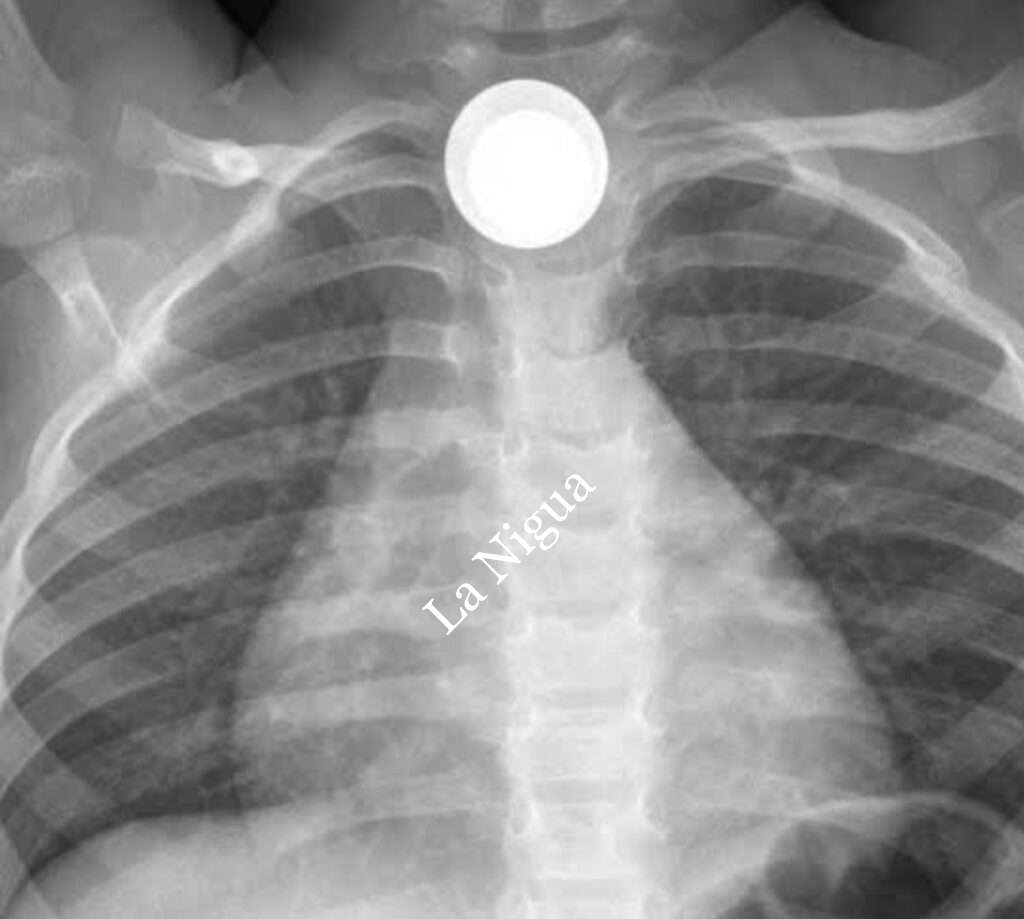

Cómo graves es reportado el estado de salud de una menor de edad que por ACCIDENTE se tragó una moneda y tuvo que ser trasladada al hospital comunitario de Coatzacoalcos para su atención médica.

De acuerdo a información obtenida por este medio, fue en una vivienda de la Colonia Agraria donde una menor de 3 años por accidente se tragó una moneda, y en un principio su madre la llevó a la Cruz Roja dónde fue canalizada al hospital Dr. Pedro Coronel pero al carecer de médicos especialistas fue trasladada de urgencias al nosocomio porteño.

La menor necesitaba una traqueotomía de manera inmediata para salvarle la vida ya que se le dificultaba respirar.